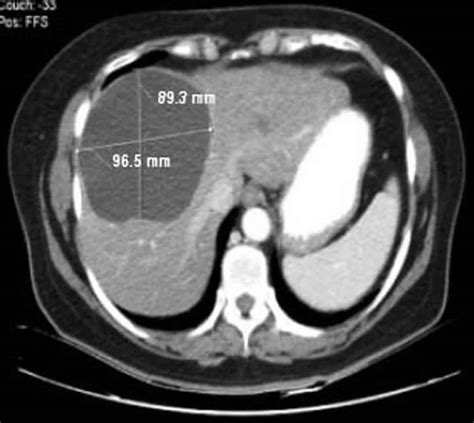

• Computed Tomography (CT) Scan: A CT scan provides detailed images of the liver and can help determine the size and location of the cyst.